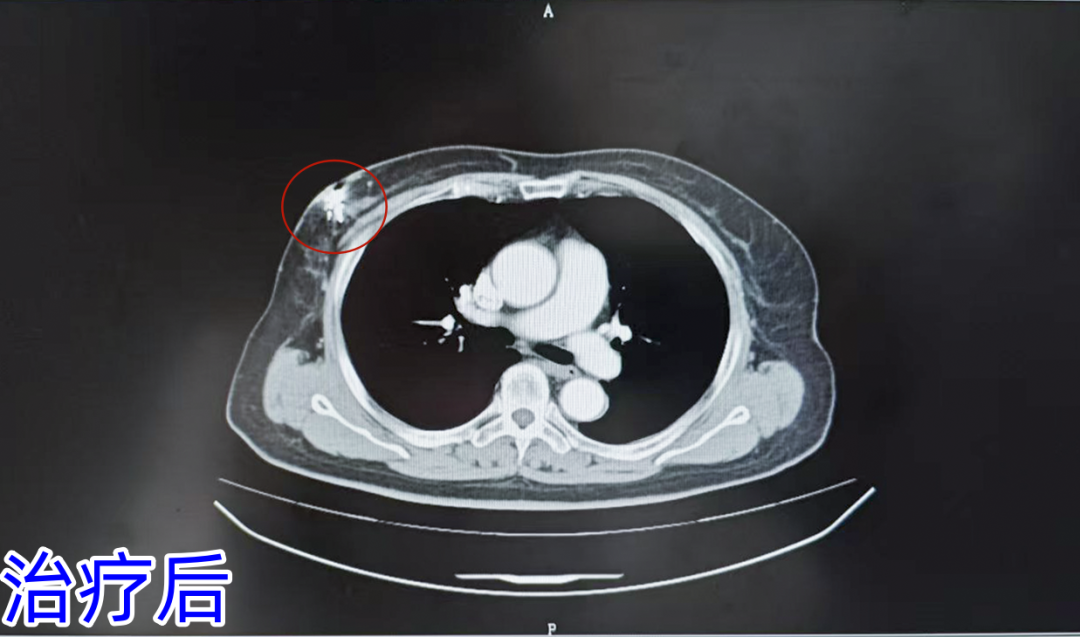

2025年1月,又在CT引导局麻下行右乳恶性肿瘤碘125放射性粒子植入术。70粒碘125放射性粒子(0.6mci)被精准地植入肿瘤内部,持续释放着射线,精准地杀灭肿瘤细胞。